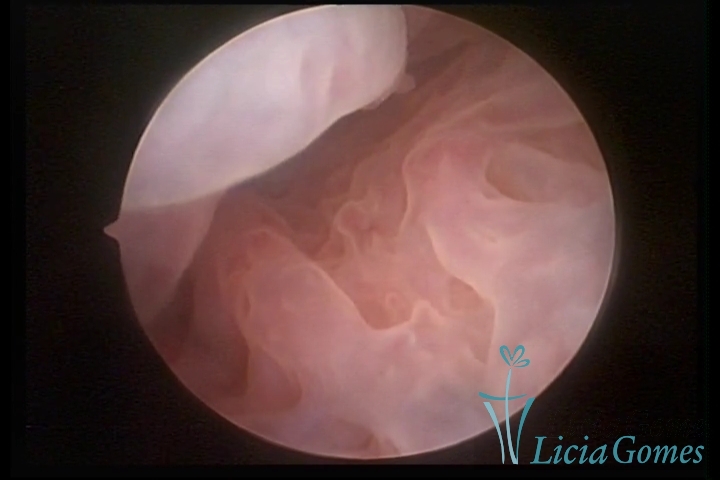

Primeira porção ou setor proximal ou setor inferior:

Durante a fase proliferativa, encontramos muco claro e cristalino pouco aderente à óptica. As criptas e as papilas apresentam-se um pouco edemaciadas e vascularizadas, micro vesicular, lembrando cachos de uva.